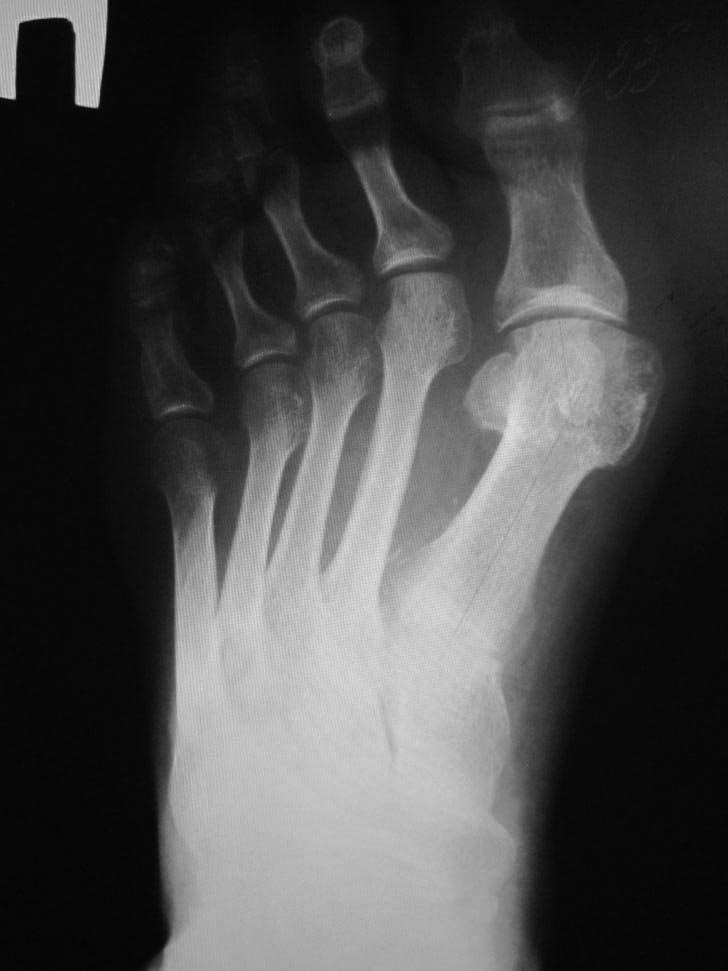

Hallux valgus+грибковое поражение 2 пальца

Больной 67 лет обратился с просьбой удалить 2 палец, так как уже целый

год испытывает сильные боли в области 2 пальца при ходьбе. Лечение у

дерматолога оказалось не эффективным.

Вальгусная деформация 1 пальца стопы беспокоит тоже пациента, но в

гораздо меньшей степени.

Уважаемые коллеги - подскажите наиболее разумную тактику лечения.